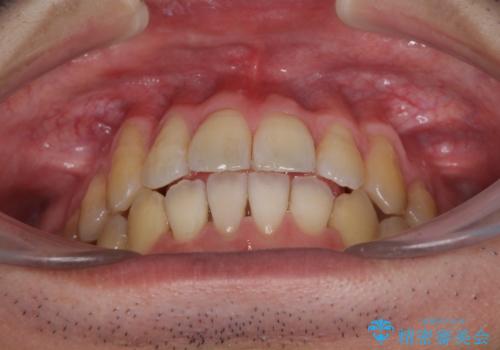

- 上下の前歯の反対咬合を気にして来院された患者様です。

インビザラインを用い、下顎はIPR(歯と歯の間を削る)と歯列全体を後方に移動させ、上顎は前歯を持ち上げることで、反対咬合を改善していくこととしました。

八重歯の歯根が見えている点も気になっているので、矯正歯科治療後に歯肉移植による根面被覆を行うこととしました。

矯正治療により元々気になっていた八重歯と、反対咬合が改善された歯の2本に対して根面被覆を行い、審美面の改善も達成しました。